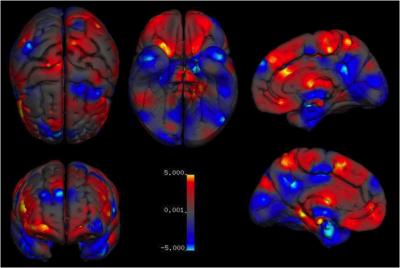

They found that males on average have larger total brain volumes than women (by 8-13%). On average, males had larger absolute volumes than females in the intracranial space (12%; >14,000 brains), total brain (11%; 2,523 brains), cerebrum (10%; 1,851 brains), grey matter (9%; 7,934 brains), white matter (13%; 7,515 brains), regions filled with cerebrospinal fluid (11.5%; 4,484 brains), and cerebellum (9%; 1,842 brains). Looking more closely, differences in volume between the sexes were located in several regions. These included parts of the limbic system, and the language system.

Specifically, males on average had larger volumes and higher tissue densities in the left amygdala, hippocampus, insular cortex, putamen; higher densities in the right VI lobe of the cerebellum and in the left claustrum; and larger volumes in the bilateral anterior parahippocampal gyri, posterior cingulate gyri, precuneus, temporal poles, and cerebellum, areas in the left posterior and anterior cingulate gyri, and in the right amygdala, hippocampus, and putamen.

By contrast, females on average had higher density in the left frontal pole, and larger volumes in the right frontal pole, inferior and middle frontal gyri, pars triangularis, planum temporale/parietal operculum, anterior cingulate gyrus, insular cortex, and Heschl's gyrus; bilateral thalami and precuneus; the left parahippocampal gyrus, and lateral occipital cortex.